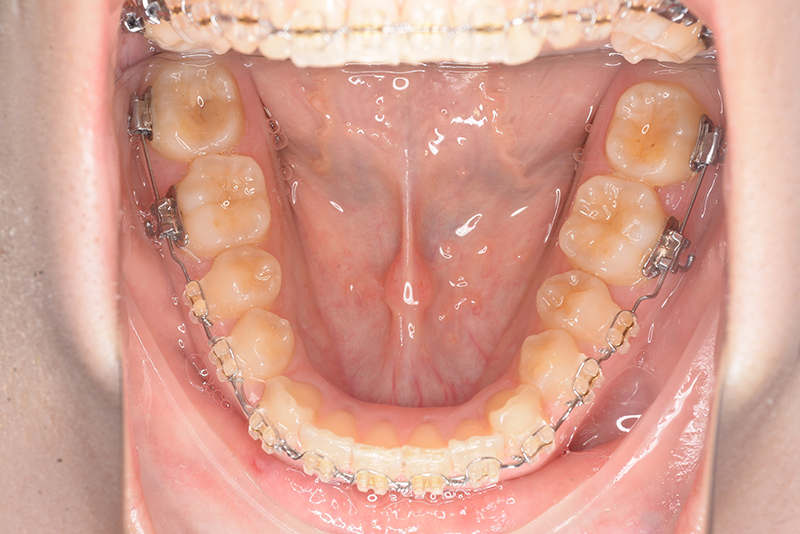

動的治療時(PLASによる上顎歯列遠心移動)

動的治療時

(PLASによる上顎歯列遠心移動)

IOP

使用装置 0.018" × 0.025" standard edgewise

その他装置 TAD(インプラントアンカー)PLAS

口腔内ゴムの使用 6ヵ月